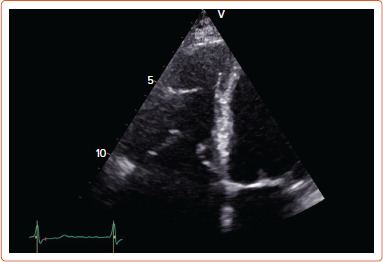

Abstract Image